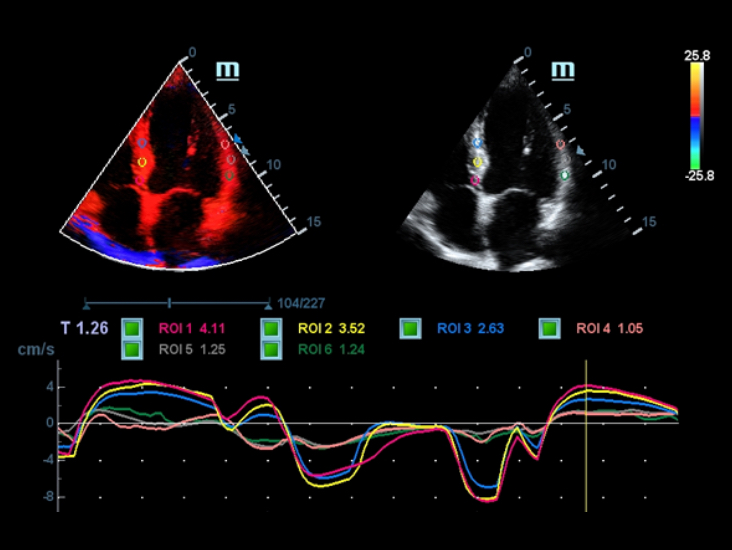

G?owice ComboWave